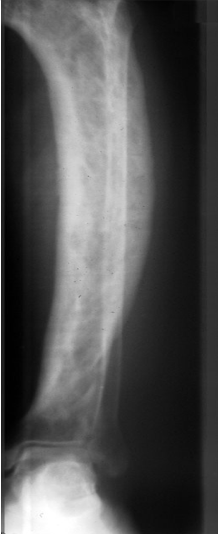

A 57 year old female with right leg pain for the last 3 months comes to see you. During your physical exam you notice anterior bowing of the tibia, warmth and localized tenderness over the skin of the bone. You order an x-ray and it shows expansion and alternating areas of osteosclerosis and osteolysis. Why is this person at risk for fractures?

This is Paget’s Disease. Rampant osteoblast overcompensation for initial osteoclast overactivity creates a disorganized, weak and mosaic pattern of woven bone. Although the woven bone is later converted to lamellar bone, it is still weak and prone to fracture.

What bones are typically affected in Paget’s disease?

Skull, tibia and pelvis.